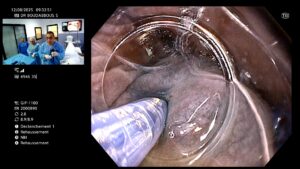

🔍 Déroulement de la procédure

- Réalisée sous anesthésie générale.

- Un endoscope flexible est introduit par la bouche.

- Le médecin crée un tunnel sous la muqueuse œsophagienne.